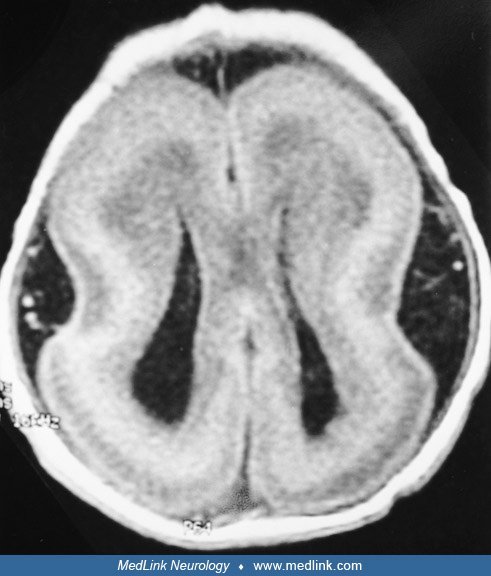

Lissencephaly

Diagnosis of lissencephaly